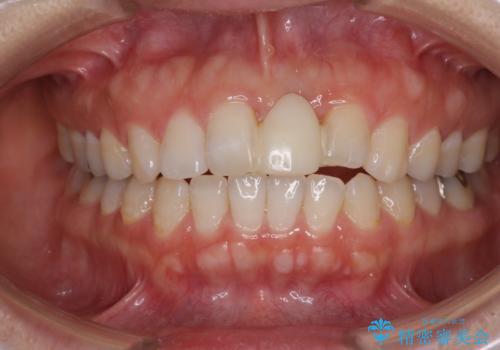

- 接着タイプの前歯のブリッジが不自然であるとのことで来院された患者様です。

欠損部の歯肉が窪んでいるため、歯肉移植により形態を改善し、オールセラミックブリッジにて補綴することとしました。

事前に装着されていた接着タイプのブリッジは、歯の切削量が少ない反面、接着界面から虫歯が進行しやすく、脱落リスクが高くなるというデメリットがあります。